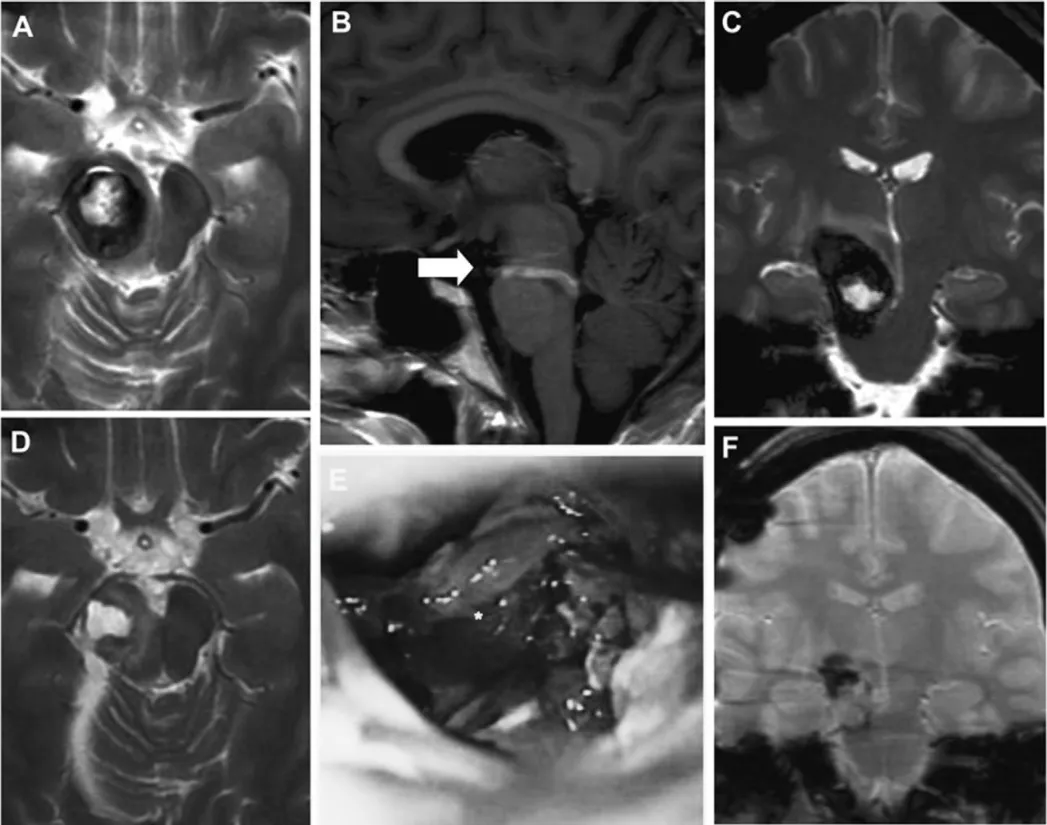

二次手术术前MRI(A-C)、术中显微镜视野(E)、术后MRI(D、F)

术后患者症状改善,二次术后1年随访,患者状况良好,仅遗留轻度左侧偏瘫后遗症。